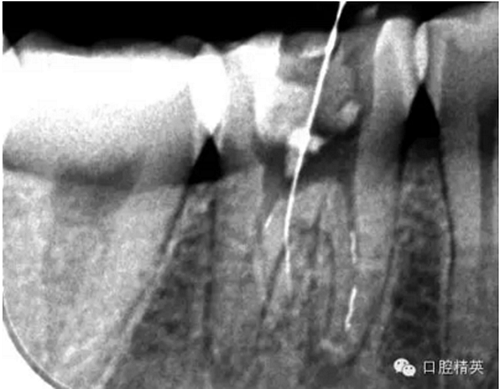

近舌8號(hào)k挫疏通,根尖部彎曲,我花費(fèi)時(shí)間2小時(shí)疏通。我個(gè)人覺得根管能否被疏通,第一個(gè)重要因素是時(shí)間,因?yàn)樽鳛檠荔w牙髓的醫(yī)生,首先就是需要的就是耐心。我個(gè)人覺得耐心是非常重要,因?yàn)楹芏喔鼙皇柰〞r(shí),都是我們快要放棄的時(shí)候。所以我每次都會(huì)安慰自己快好了,快好了,就差一點(diǎn)點(diǎn),在堅(jiān)持一會(huì)兒就好了??梢哉f沒有耐心,想做好牙體牙髓,我個(gè)人覺得很難很難。第二個(gè)就是手法,不知道大家啟用挫是什么挫,一般我個(gè)人認(rèn)為,最好從8號(hào)開始疏通,這樣不容易在狹窄的根管內(nèi)形成臺(tái)階(如果有條件的可以從6號(hào)開始)。

這個(gè)病例難以疏通在于根中上段堵塞,根尖下段有臺(tái)階的形成,感覺不到彎曲的方向。首先我們處理根上段,我們可以采取的方法是先預(yù)備跟中上段,將它擴(kuò)開來,這樣有利于根尖下段的預(yù)備,建立良好的視野。對(duì)于根尖下段的臺(tái)階和彎曲 ,8號(hào)挫預(yù)彎,第二步要知道根管彎曲的方向,沿著根管彎曲的方向疏通。特別是有臺(tái)階的地方,一定不要硬來,慢慢旋轉(zhuǎn)找到根管彎曲的方向(結(jié)合x線片)避開臺(tái)階,一定要記住慢慢旋轉(zhuǎn)角度越小越好,正旋逆旋找“緊點(diǎn)”,有經(jīng)驗(yàn)的醫(yī)生大概都知道,找到了“緊點(diǎn)”就等于找到了希望。手法一定要輕柔不易暴力!切記切記!戒浮戒躁(這句話也是特別要告訴我自己)。